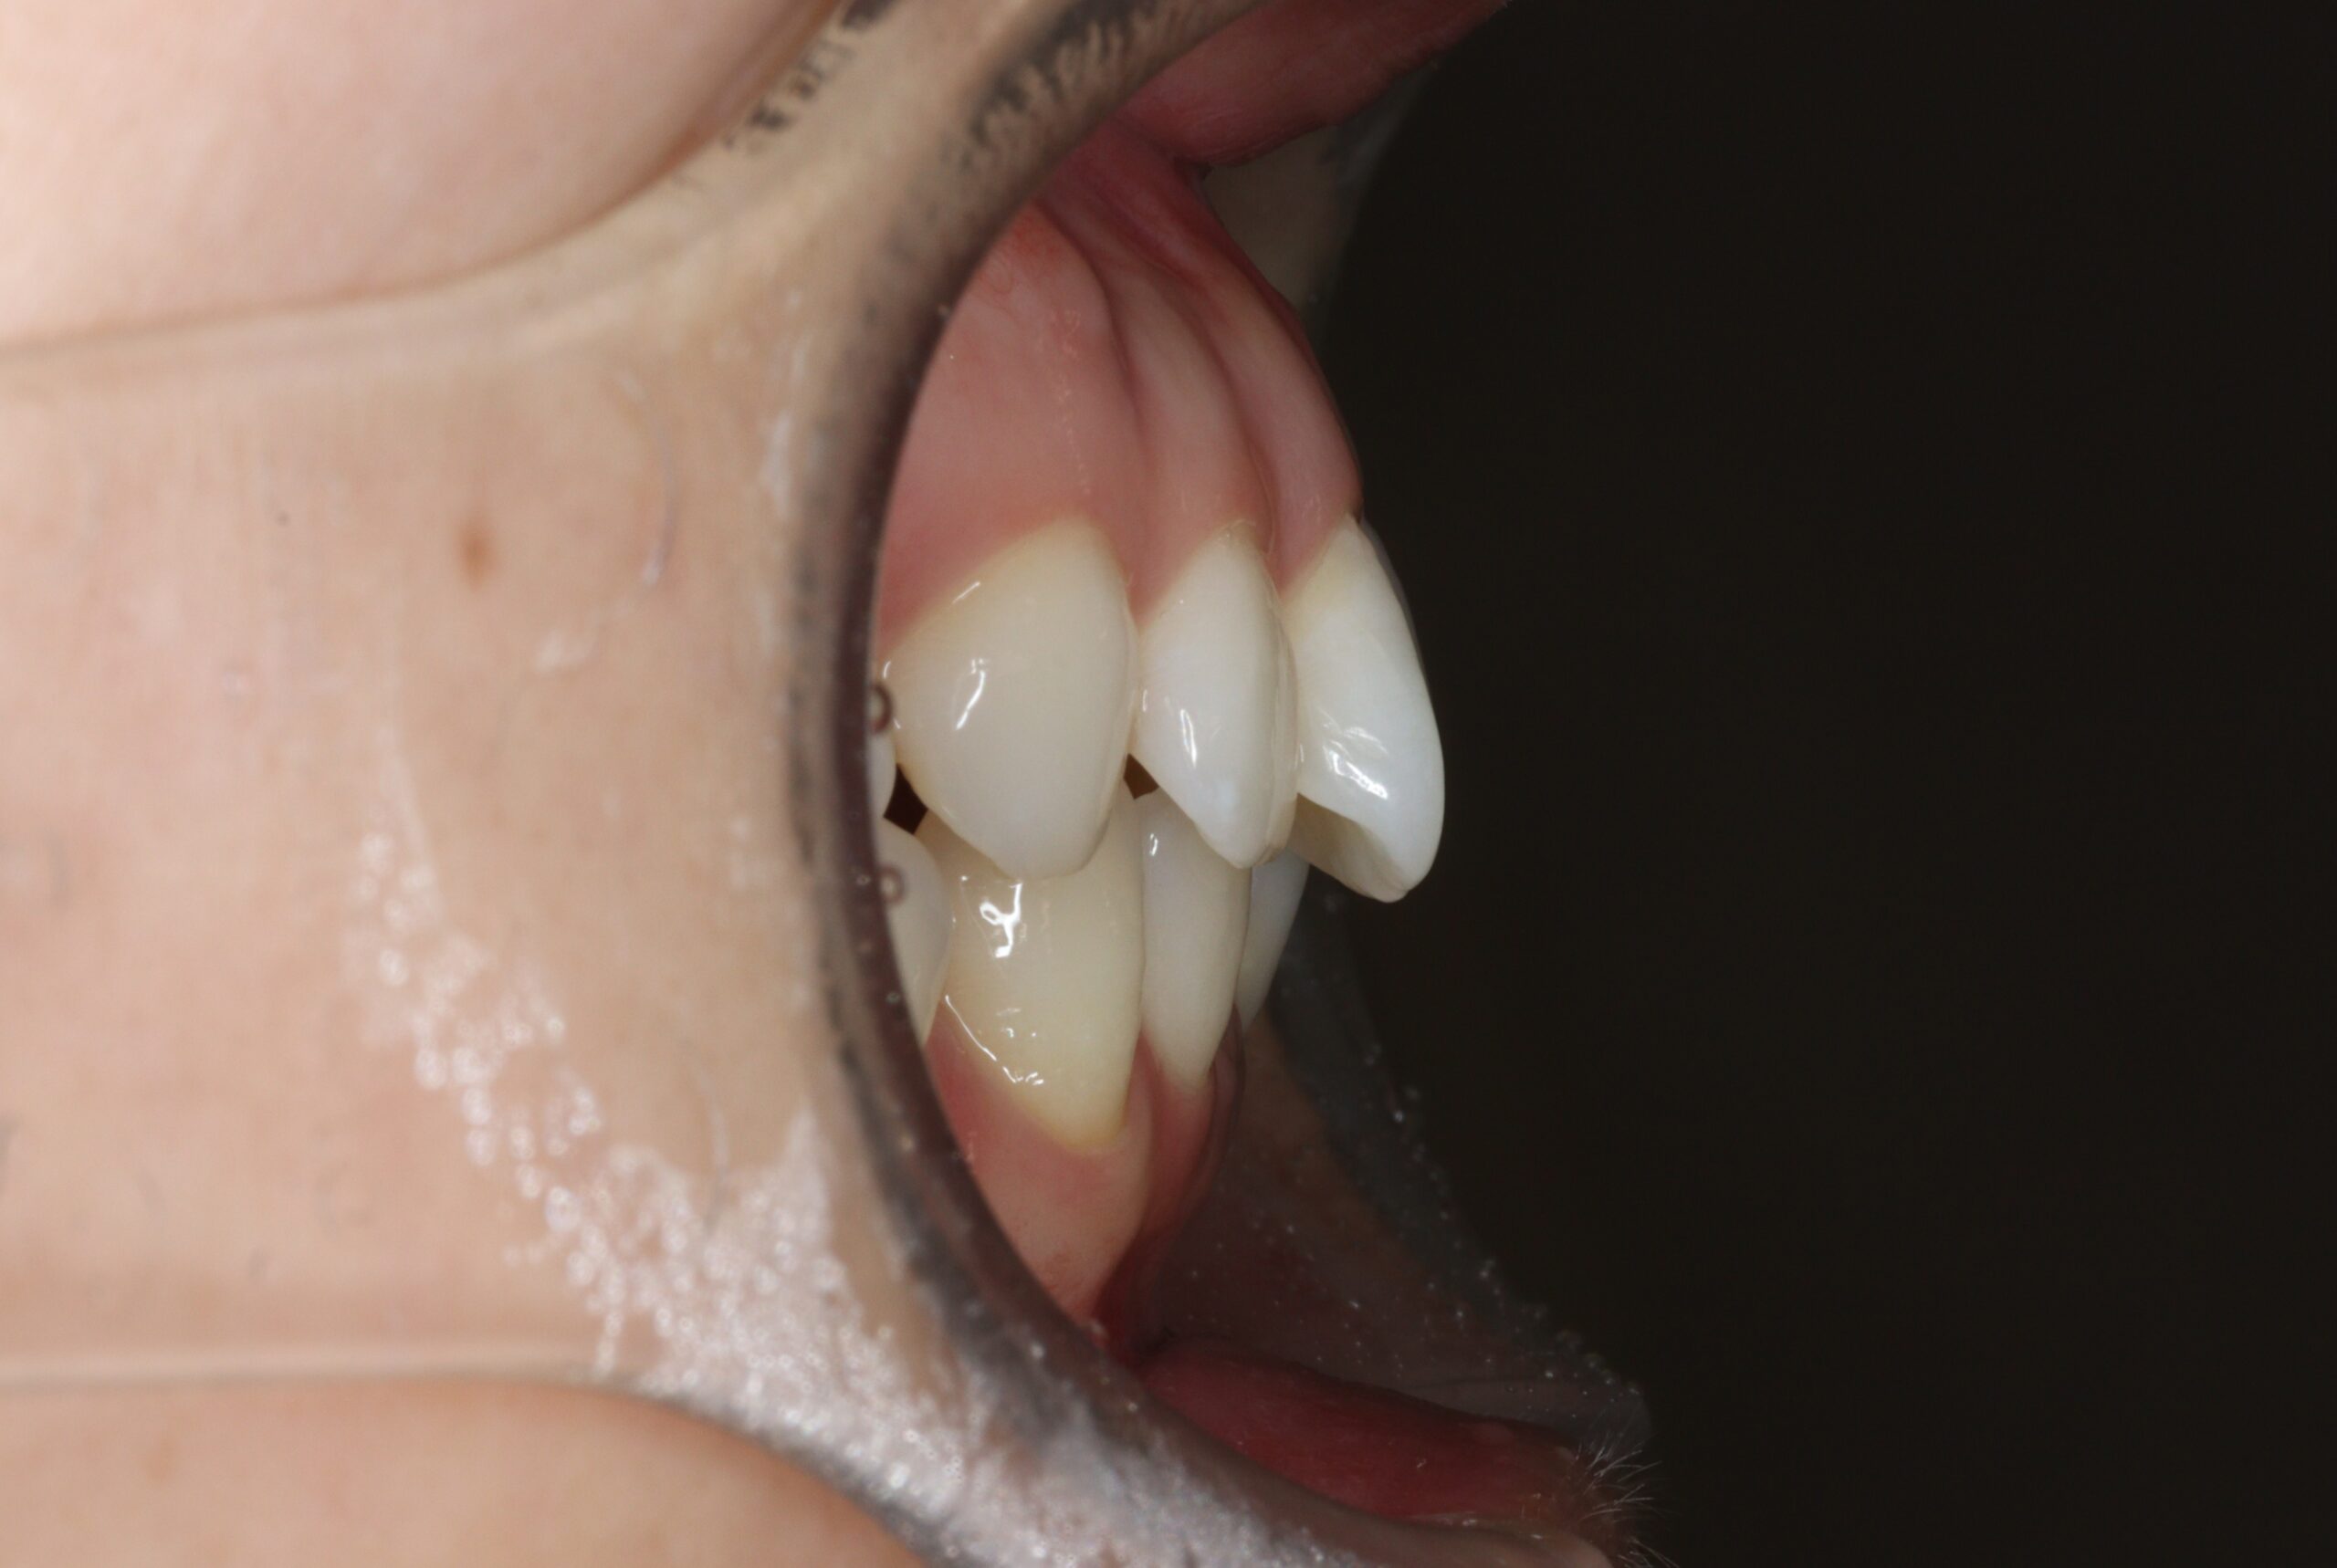

矯正術前:右側

矯正術後:右側